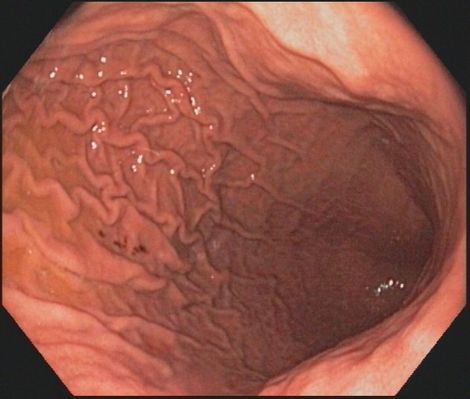

Koloskopie (Darmspiegelung): Die Darmspiegelung ist die effektivste und zuverlässigste Methode, Darmkrebs zu verhindern oder in einem sehr frühen Stadium zu erkennen. Werden Darmpolypen - die Vorstufen von Darmkrebs - während der Koloskopie entdeckt, können sie in den meisten Fällen sofort endoskopisch entfernt werden. Zur Früherkennung von Darmkrebs bezahlen die gesetzlichen Krankenkassen ab dem 56. Lebensjahr regelmäßige Vorsorgekoloskopien. Wenn in der Familie Fälle von Darmkrebs aufgetreten sind oder eine genetische Vorbelastung besteht oder besondere Risikofaktoren vorliegen - etwa eine chronisch-entzündliche Darmerkrankung - werden Vorsorgekoloskopien früher und in kürzeren Abständen durchgeführt.

Bei Änderung der Stuhlgewohnheiten oder Blutungen und bei Verdacht auf eine chronisch entzündliche Darmerkrankung ist die Darmspiegelung die wichtigste Maßnahme, die in ihrer Aussagekraft durch keine andere Methode zu ersetzen ist.

Bei der Darmspiegelung wird ein dünner, biegsamer, Schlauch (das Koloskop), über den After in den Darm eingeführt und vorsichtig bis zum Übergang vom Dünndarm zum Dickdarm geschoben ("Bauhin'sche Klappe"). Dabei wird etwas Luft in den Darm geblasen, damit er sich entfaltet. Dann wird das Endoskop sehr langsam zurückgezogen und die Darmwand genau begutachtet. Von veränderten Schleimhautbereichen werden mit Hilfe einer kleinen Zange Gewebeproben entnommen, Darmpolypen können sofort entfernt werden. In einigen Fällen kann durch Aufbringen von Farbe eine bessere Beurteilbarkeit erreicht werden (Chromoendoskopie).